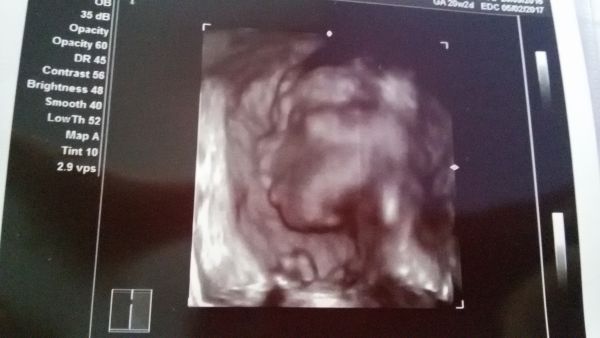

Ahoj maminky. Dnes jsem byla na druhém screeningu a vše je v pořádku. :-) prcek má 330 gramů. Cm nevím :-) pohlaví nepotvrzeno moc sebou šil měl nožky v tureckým sedu:-) ale snad tam ten chlapeček z prvního screeningu je :-D Krásně cítím pohyby. Je to divoch :-) přikládám fotecku oblicejiku s ručičkou :h: